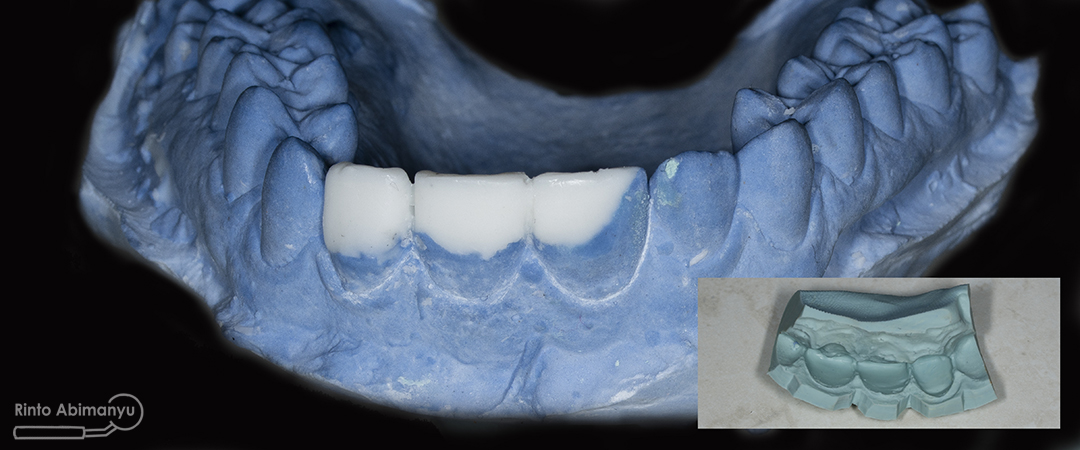

Wax up ini merupakan proses yang penting bila kita berhadapan dengan kasus yang kondisi giginya tidak utuh, dari sanalah nanti kita mendapatkan visualisasi perkiraan hasil akhir perawatan… Wax up bisa dilakukan sendiri bila kita mempunyai alat dan bahan yang diperlukan atau bisa dikirimkan ke lab… Tapi saya mempunyai istri yang juga seorang prostodontis jadi saya minta tolong dia untuk melakukan wax up hehehe :p

Hasil wax up dan pada insert terlihat hasil cetak untuk silicone index

Model yang sudah diwax up kemudian saya cetak dengan putty double impression yang nanti cetakan tersebut dijadikan sebagai silicone index pembuatan mahkota sementara…